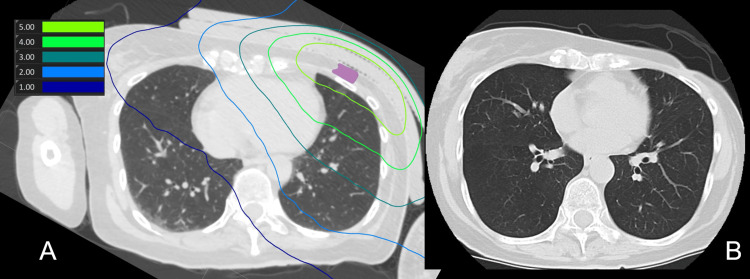

近期,一项发表于《Critical Reviews in Oncology/Hematology》的Meta分析,系统评估了硼中子俘获疗法(BNCT)治疗局部复发性头颈癌(LRHNC)的疗效与安全性。